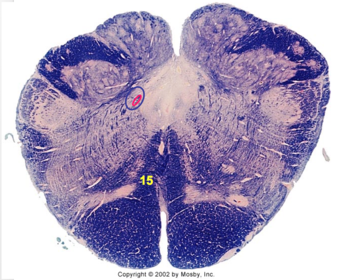

| Spinal tract of V | |

| Spinal nucleus of V | |

| Medial vestibular nucleus | |

| Inferior vestibular nucleus | |

| Dorsal cochlear nucleus | |

| Ventral cochlear nucleus | |

| Inferior olivary complex | |

| Inferior cerebellar peduncle | |

| CN IX | |

| Anterior spinocerebellar tract | |

| Central tegmental tract | |

| Olivary internal arcuate fibers | |

| Solitary tract | |

| Abducens root fibers | |

| Longitudinal pontine fibers (corticospinal tract) | |

| Transverse pontine fibers (dark fibers) | |

| Pontine nuclei (pale) | |

| Medial lemniscus | |

| ALS | |

| Trapezoid body | |

| Ventral trigeminothalamic tract | |

| Superior olive | |

| Facial nerve root fibers - descending | |

| Facial motor nucleus | |

| Interposed nuclei | |

| Medial longitudinal fasciculus | |

| Facial nerve root - internal genu | |

| Abducens nucleus | |

| Lateral vestibular nucleus | |

| Superior vestibular nucleus | |

| Superior cerebellar peduncle | |

| Dentate nucleus | |

| Fastigial nucleus | |

| Middle cerebellar peduncle | |